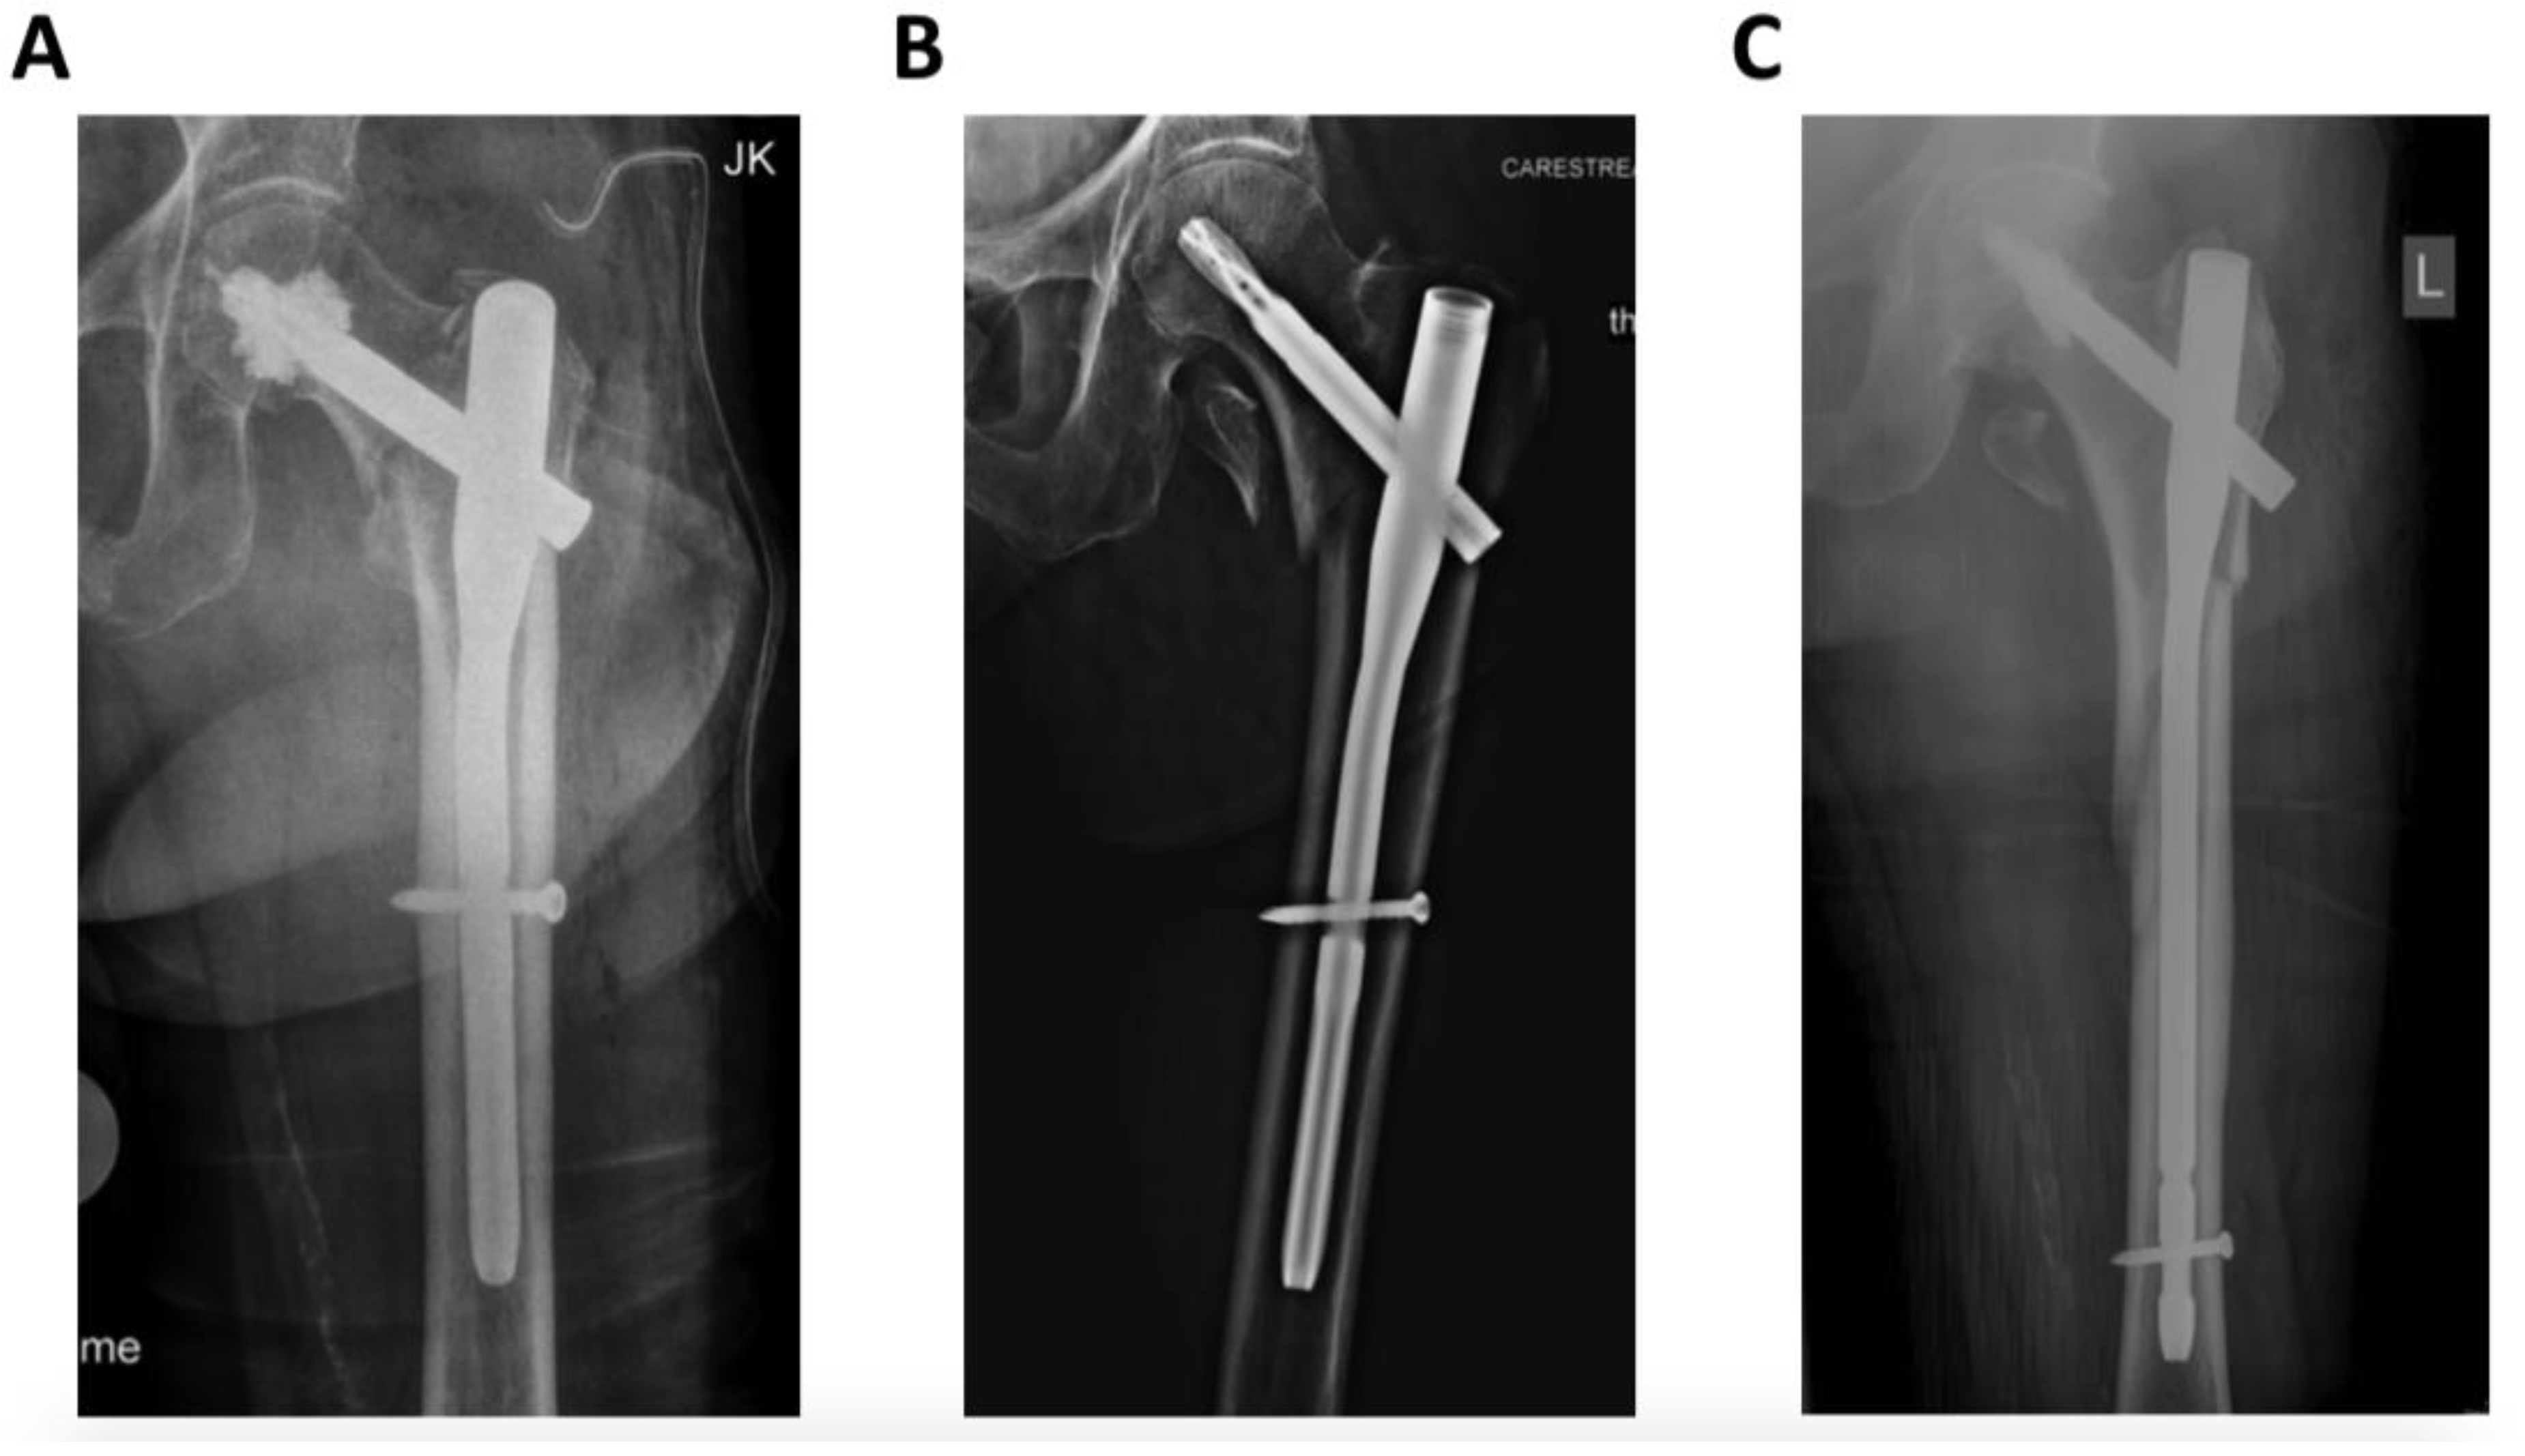

In all cases, surgery was performed under general anesthesia by trauma specialists (seven senior trauma surgeons), according to the AO principles of fracture management. An extension table was used for fracture reduction with open or closed reduction depending on the fracture pattern. Cephalomedullary fixation was achieved with the Proximal Femoral Nail Antirotation (PFNA, DePuy/Synthes, Umkirch, Germany) with additional bone cement augmentation of the helical blade in case of poor bone quality, according to the surgeons’ intraoperative findings (Figure 1).

Figure 1.

Radiographic images of different trochanteric fracture patterns according to the revised AO/OTA Classification. (A) = 31A1; (B) = 31A2; (C) = 31A3.